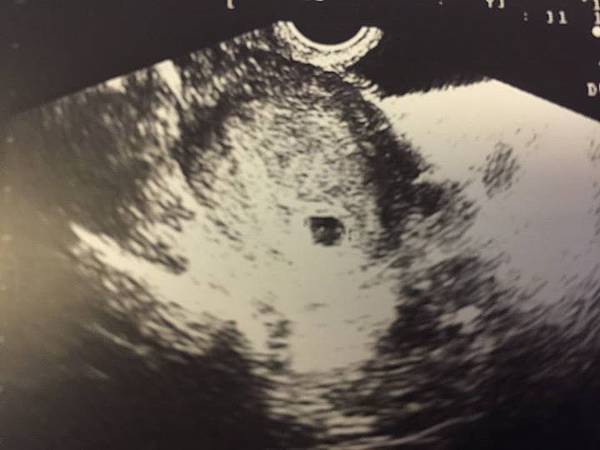

這是寶寶的第一張照片;一顆小胚胎